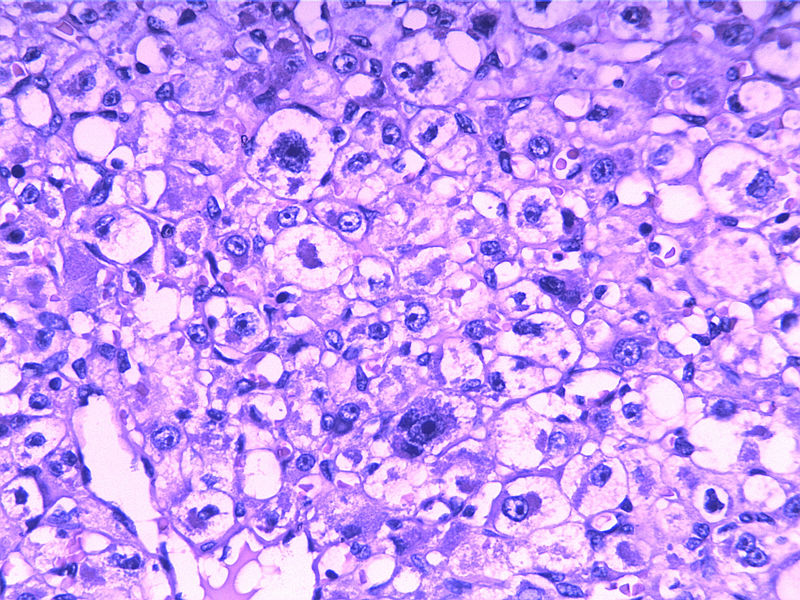

女30Y,大腿肿物5Y,直径3cm

• 女30Y,大腿肿物5Y,直径3cm图3

图3

Micro description

● Well circumscribed but non-encapsulated with infiltrative borders

● At least focal typical liposarcomatous areas

● Pleomorphic cells cover > 65% of cut surface with MFH-like, round cell liposarcoma-like (without vascular network), spindle cell liposarcoma-like or epithelioid cells (Mod Path 1999;12:722)

● Usually high grade with enlarged round to bizarre nuclei; tumor necrosis common; median 25 mitotic figures/10 HPF

● May have neutrophils within giant cells, hemangiopericytic foci, extra- and intracellular hyaline droplets

本例可能是具有非典型性组织学特征的腺泡状软组织肉瘤

Enzinger and Weiss:The individual cells are large, rounded, or more often polygonal and display little variation in size and shape. They have distinct cell borders and one or more vesicular nuclei with small nucleoli and abundant granular, eosinophilic, and sometimes vacuolated cytoplasm. Mitotic figures are scarce. Rare pleomorphic tumors have been reported in the literature ——Evans HL: Alveolar soft-part sarcoma. A study of 13 typical examples and one with a histologically atypical component.  Cancer  1985; 55:912.